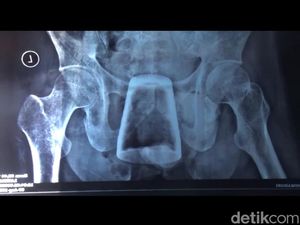

Gelas di dalam perut warga Jember, sudah dikeluarkan melalui operasi. Namun banyak warga yang masih mempercayai peristiwa tersebut gara-gara santet.